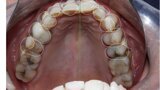

Figure 7 Mandibular occlusal view before treatment